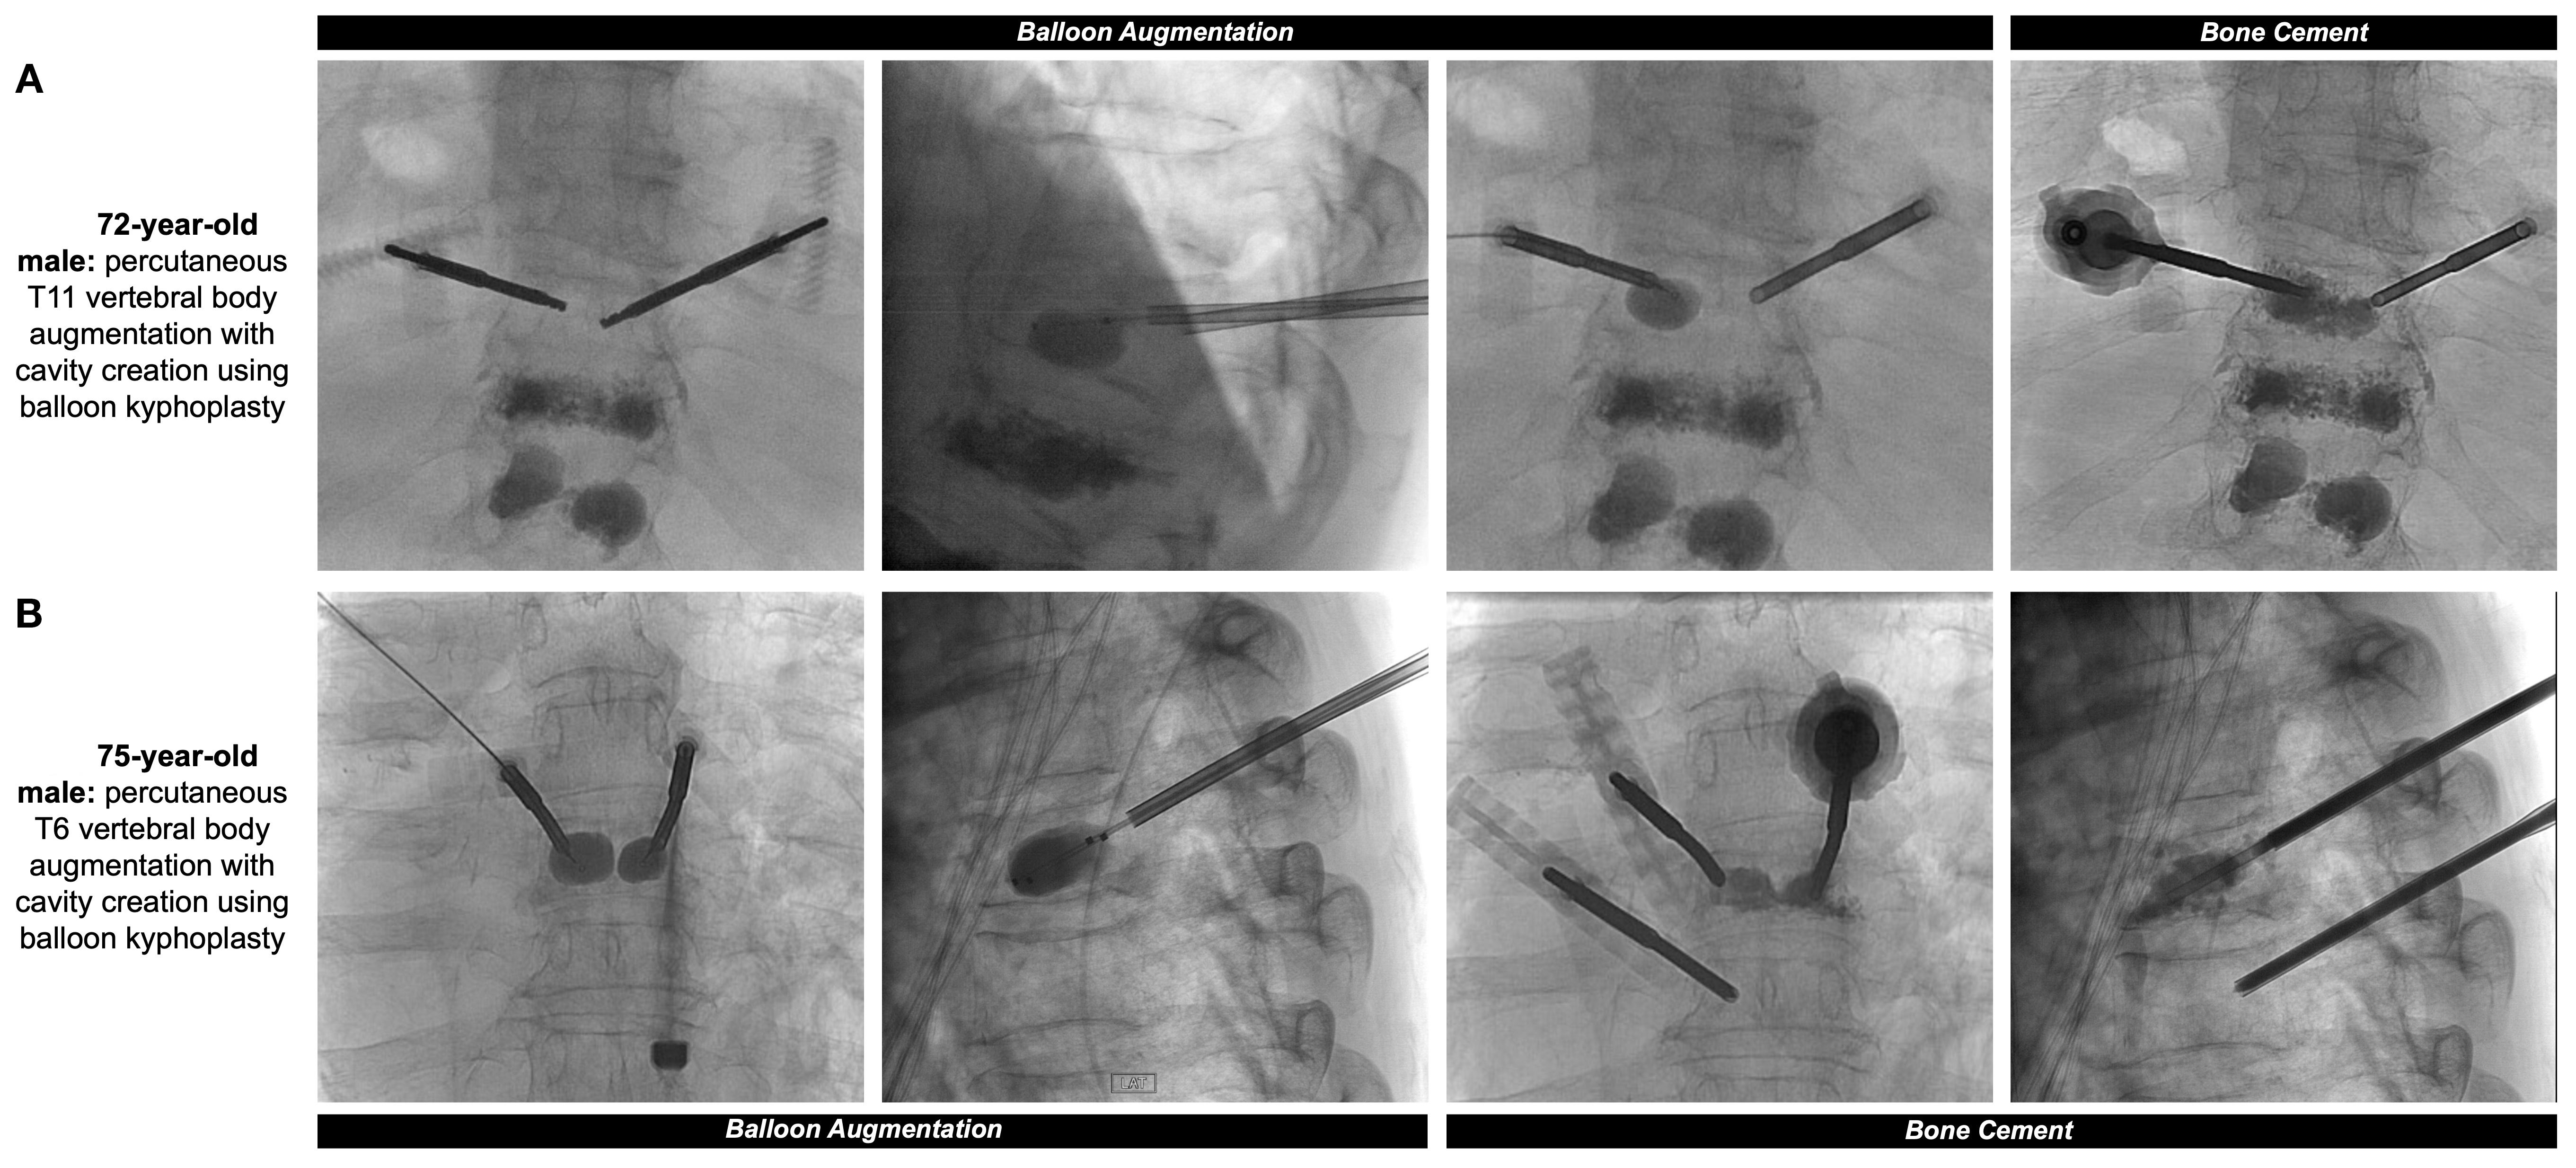

Treatment of painful, pathologic vertebral fractures in patients with MM can include vertebroplasty and kyphoplasty, particularly when lytic lesions occur in regions susceptible to compressive forces. In vertebroplasty, bone cement made up of polymethylmethacrylate (PMMA) is injected directly into the fractured vertebral body. In comparison, kyphoplasty first comprises placement of an inflatable balloon into the vertebral body with creation of a potential space or cavity, prior to injecting PMMA or absorbable calcium phosphate (13) (Figures 1A, B, 2). The primary objective of both procedures is to consolidate and stabilize pathologic bone fractures to achieve measurable pain relief. Notably, kyphoplasty also aims to restore vertebral body height via balloon inflation (3, 13). The most common complication of kyphoplasty is cement leakage, noted in 18% of treated vertebral levels in a 2009 study involving 76 MM patients. Rare but serious sequelae of leakage include motor deficits from spinal cord compression or pulmonary embolism, reported in 2% to 13% of cases (13, 14).

Figure 1. (A) 72-year-old male with a past medical history of MM with painful thoracic and lumbar spinal metastases and multilevel compression deformities. Two 11-gauge coaxial needles were introduced into the posterior third of the T11 vertebral body, followed by hand drills and bilateral 10mm augmentation balloons. PMMA was then injected into the T11 vertebral body with adequate filling demonstrated. Pre- and post-operative sagittal surveys are included in Figure 2. (B) 75-year-old male with a past medical history of MM with multiple compression fractures. The same process as the previous patient was repeated at the level of the T6 vertebral body, with small substitutions including 10-gauge coaxial needles and 15mm augmentation balloons.